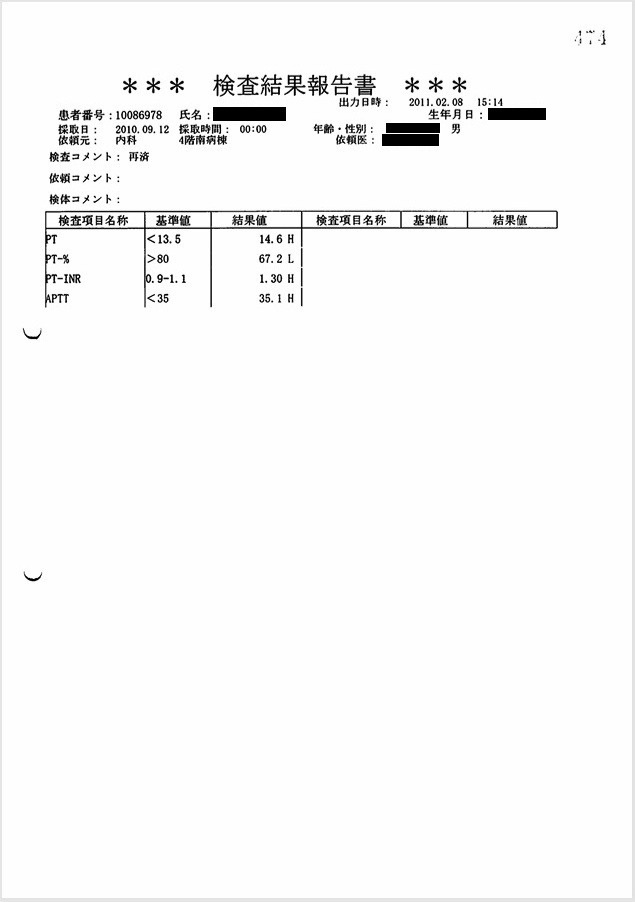

- 9月12日:出血傾向はごく軽度

PT-INR 1.3, APTT 35 sec, 血小板3.6万/μl, Hb 8.2 g/dl:出血傾向はごく軽度で硬膜下血腫の自然発生は否定的。この時、父は意識がなく自ら動くことはできない状態であったため、頭部を殴打された可能性しか残らない。

証拠:血液検査データ(9月12日)

この時、撮影された頭部CTで急性硬膜下血腫が認められた。これが父の直接の死因となった。 医師からもその説明があったが、 直接の原因と推定される「頭部打撲」には一切言及がなく(録音記録あり)、 DIC(播種性血管内凝固)に伴う出血傾向による自然出血とのことだった。 しかしほぼ同時に行われた血液検査では、「PT-INR 1.3, APTT 35 sec, 血小板3.6万/μl」と 出血傾向はごく軽度であり、自然発生的に頭蓋内に出血を起こす可能性は皆無と言ってよい。